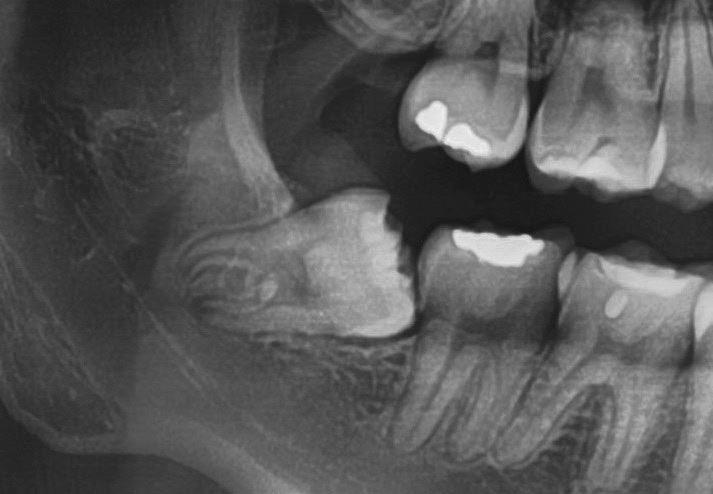

Questo è un paziente di 22 anni ed essendo un amico, ho potuto ben documentare il caso con il suo consenso: il suo dente del giudizio inferiore sinistro è stato estratto utilizzando il manipolo dritto. Figg. 143-149

Figg. 143-149 - Caso 1, paziente di 22 anni: tecnica di estrazione con divisione orizzontale utilizzando il manipolo dritto. Fig. 143 Fig. 144 Fig. 145 Fig. 146 Fig. 147 Fig. 148 Fig. 149

Dalla radiografia (Fig. 166) sembrava che il dente avesse due radici separate, quindi è stato eseguito un taglio orizzontale utilizzando il manipolo dritto per sezionare il dente a metà. Tuttavia, la corona si è frat-

turata poiché in realtà le radici erano unite e il dente non è stato sezionato completamente.